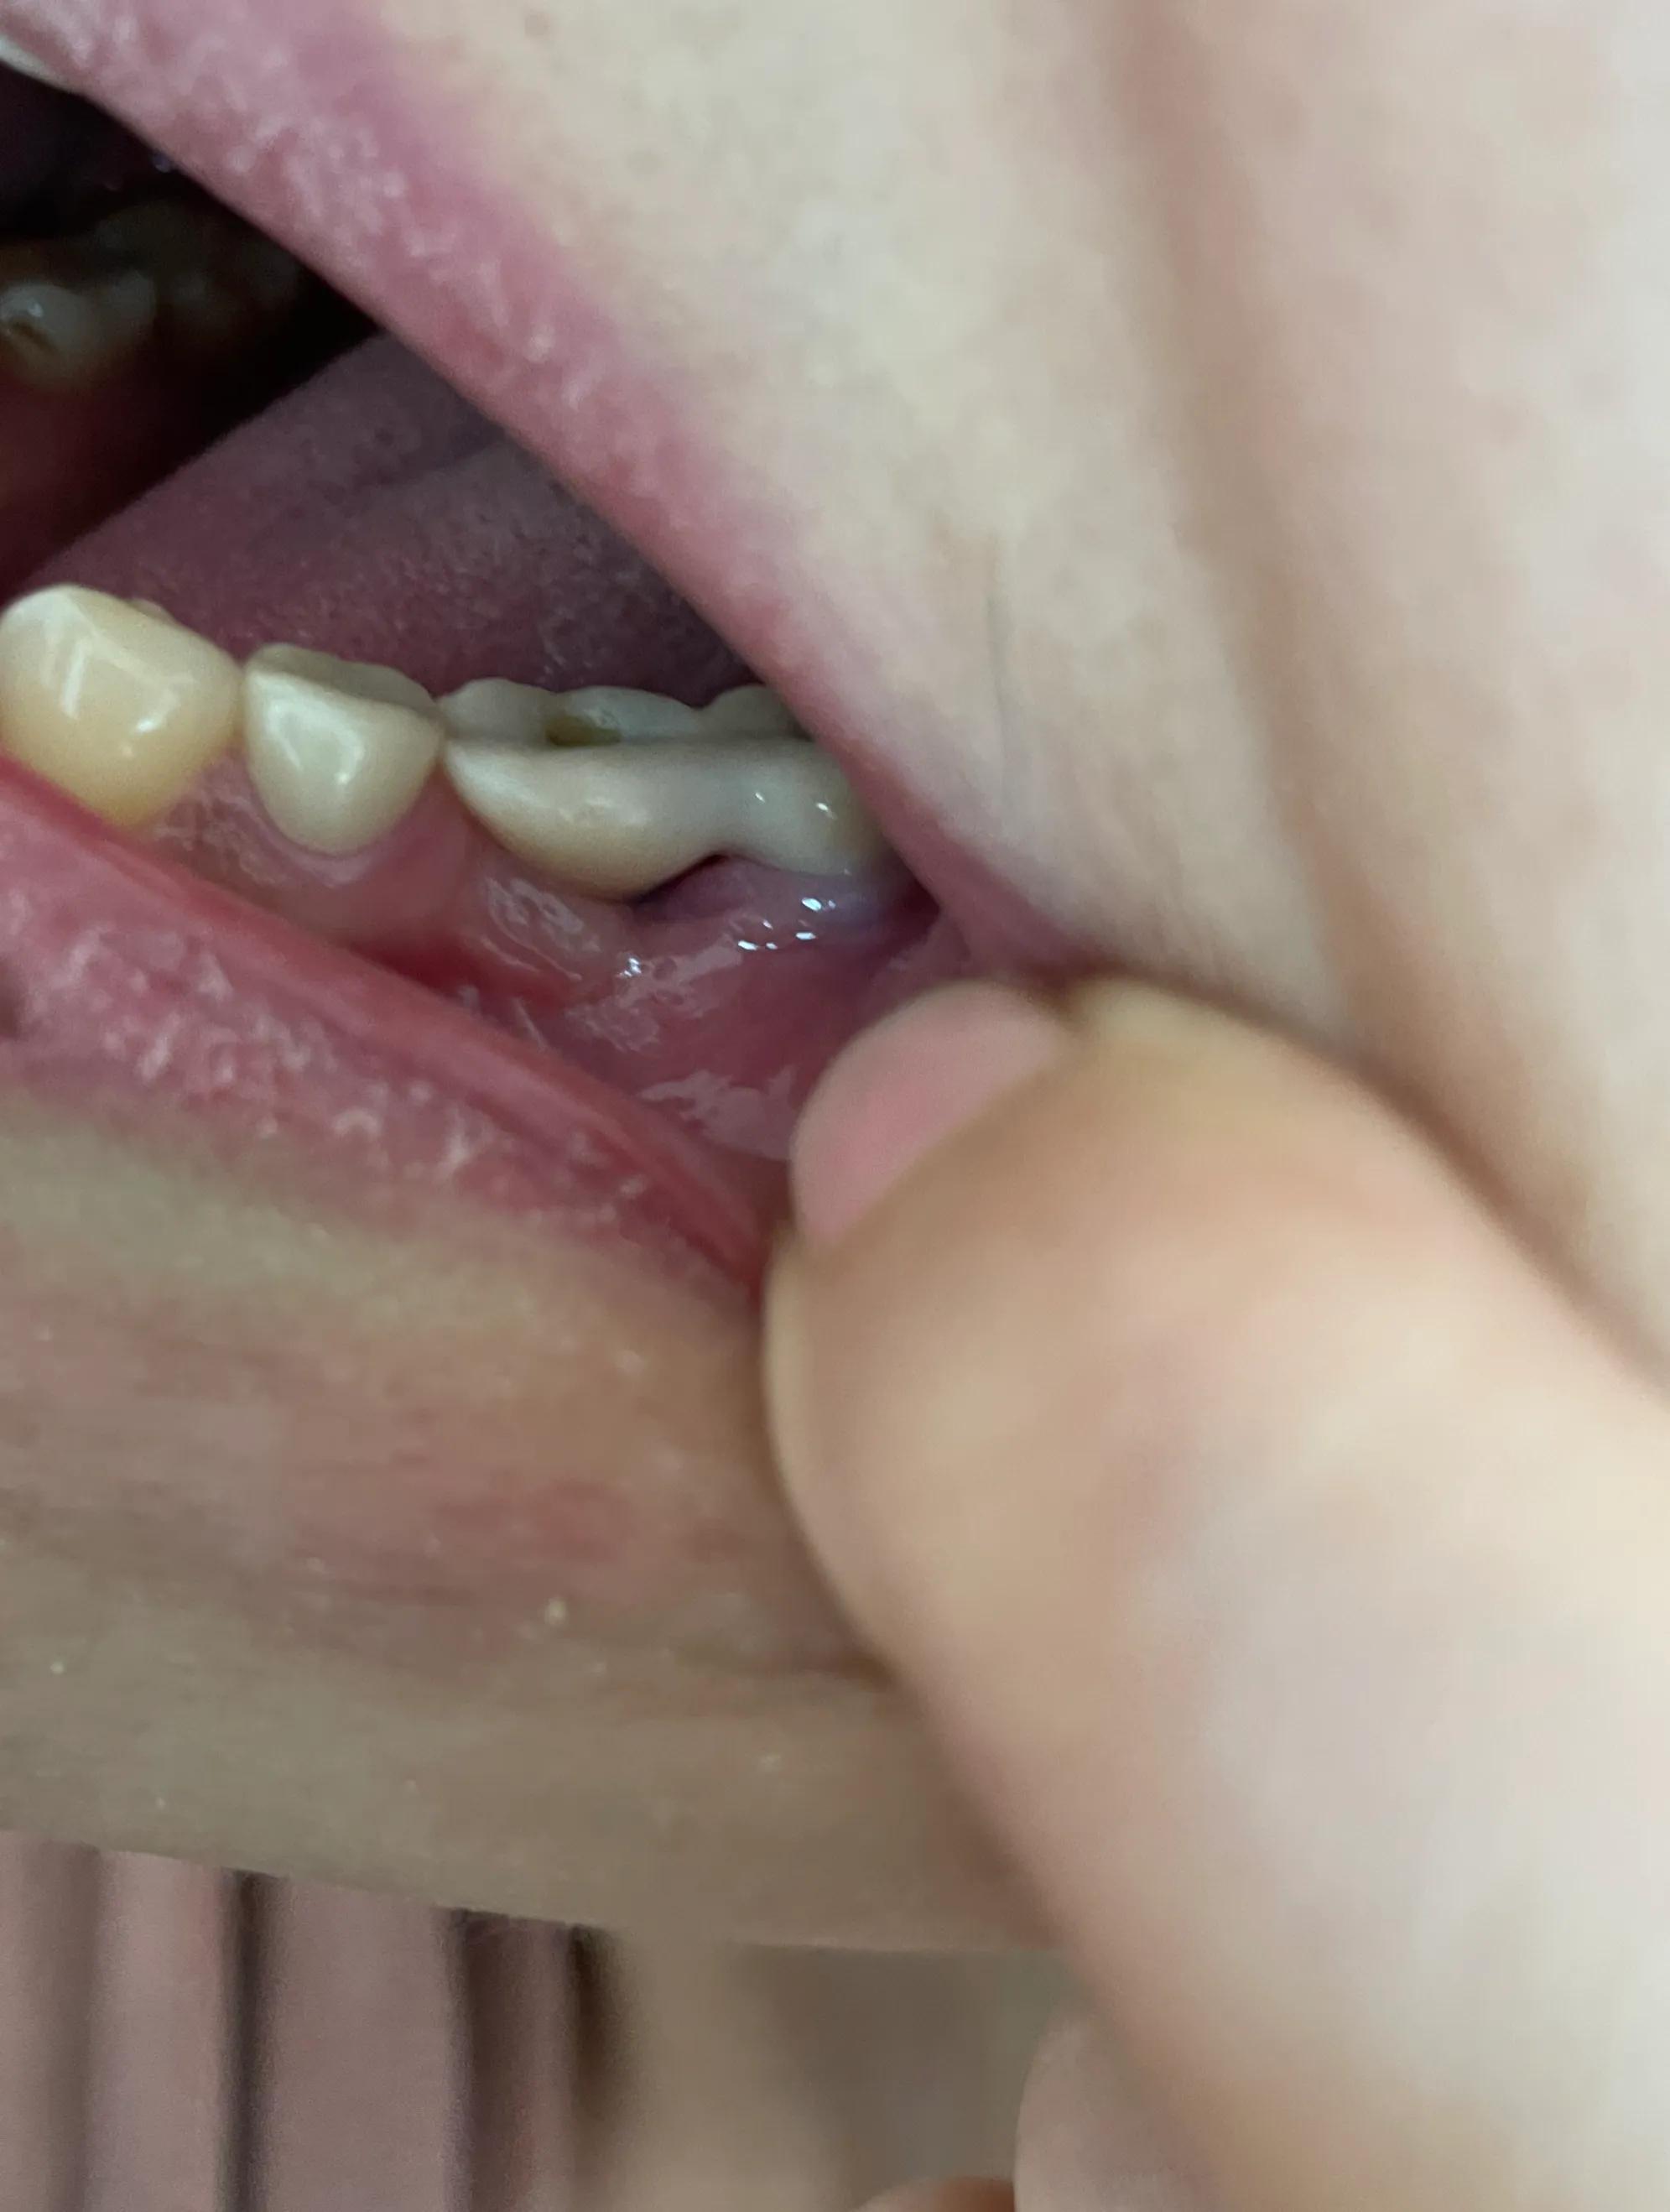

第二副牙帶好 發(fā)現(xiàn)牙齦又缺肉了 更別提貼合牙齒了 而且是一直的疼 一直難受

牙齦是外翻和牙齒分開的 顏色發(fā)白 和其他部位牙齦不是一樣顏色

我不是專業(yè)醫(yī)生 不懂他們所說的正常現(xiàn)象都包括什么 要怎么后期維護(hù) 我現(xiàn)在先不講看不見的難受 疼 先講直觀能看見的 他們哪位醫(yī)生可以做到把大米粒塞到牙齒下面 和將近半厘米的塑料條塞過他們的牙齒 吃過東西就要用沖牙器 不然隔頓就臭了

沒辦法自己又出去拍片子 找原因 看了幾家醫(yī)院 才知道連種植體也種偏了 牙冠也沒有就位………